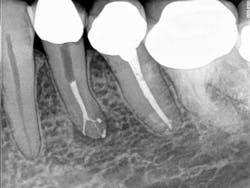

QMix 2in1 irrigation solution was used as the final irrigant, using the ProRinse® irrigation needle. The EndoActivator was used to agitate all the irrigants. ThermaSeal® Plus Ribbon® sealer and GuttaCore® obturator were used to obturate. Post space was made with a GT® Post drill.

"Since the canal bifurcated hard at the distal," he said, "Flex NTK hand files were used to prepare this area. The ability of GuttaCore to obturate the challenging apical anatomy was greatly enhanced by deep delivery of sodium hypochlorite and QMix using the ProRinse irrigation needle and the EndoActivator."

Postop